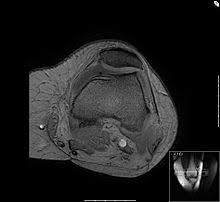

Die Tiefe des Knorpelschaden erreicht mehr als die Hälfte 50 der gesamten Knorpeldicke. Eine mögliche Ursache herauszufinden warum es überhaupt zu einer chondropathia patella kam Und 3eine Symptomlinderung. Sie können sich bei der Beugung mit den Händen auf den vorderen Oberschenkel abstützen.

Es bestehen Risse und Löcher im Knorpel diese reichen aber noch nicht bis zum Knochen. Leichte Erweichung des Knorpels undoder oberflächliche RisseFissuren im Knorpel. Das hast du aber bei beiden Übungen dabei.

Leichte Erweichung des Knorpels undoder oberflächliche RisseFissuren im Knorpel. Bei der Chondropathia patellae handelt es sich um ein Schmerzsyndrom im Bereich der Kniescheibe. Ein Knorpelschaden hinter der Kniescheibe Chondropathia patellae steht für eine krankhafte Veränderung des Knorpelgewebes. Zu Beginn bereiten die Knorpelveränderungen keine Beschwerden erst bei fortgeschrittenem Knorpelschaden kommt es zu Schmerzen. Was man nun tun sollte ist folgendes. Bei der Chondropathia patellea handelt sich um schmerzhafte degenerative Veränderungen des Gelenkknorpels an der Rückfläche der Kniescheibe Patella. Die Behandlung ist davon abhängig wie ausgeprägt die Erkrankung und die Beschwerden sind. Auch bei dieser Übung empfiehlt sich ein langsames beugen und ein schnelleres strecken. - 3 Übungen um die Kniescheibenführung zu verbessern Dysbalancen zu.

Die Kniescheiben wird nach innen gedrückt gehalten. Zu den häufigsten Bewegungsabläufen gehören in die Hocke gehen Treppen steigen hoch und runter Patienten im Bett bewegen ziehen rennen sowie schwere Betten schieben. 1 Beinpresse Sumo-Stand mit Füße hoch auf Platte mit 23-Gewicht und höherer Wdhzahl Beinwinkel immer 90 2 Abduktion mit vollem Gewicht 3 Adduktoren mit vollem Gewicht Cool da hab ich sogar noch Zeit für Cardio Rad da gut fürs Knie. Die Tiefe des Knorpelschaden erreicht mehr als die Hälfte 50 der gesamten Knorpeldicke. Normal keine erkennbaren Defekte. Ihr geht in der Regel. Auch bei dieser Übung empfiehlt sich ein langsames beugen und ein schnelleres strecken.